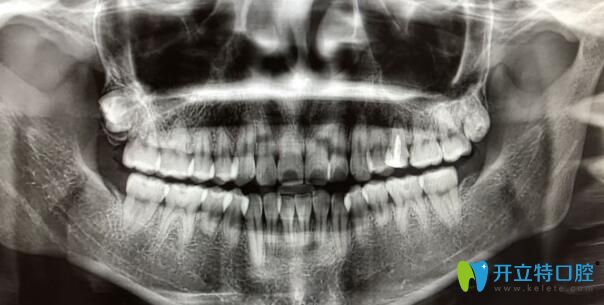

案例一:90后自述門牙牙根短做矯正感受:

首先我的門牙牙根很短,兩個(gè)醫(yī)生拒絕給我矯正的,但是我整牙欲望很強(qiáng)烈,冒著風(fēng)險(xiǎn)做了,也不知道以后會出現(xiàn)什么問題,門牙是否真的掉了,到時(shí)候再說吧,問題出了再去解決…

90后自述門牙牙根短做矯正感受

?牙齒矯正2個(gè)月:?感覺牙齒變化速度比較慢,目前牙齒還沒又松動神馬的感覺。

牙根短做矯正效果